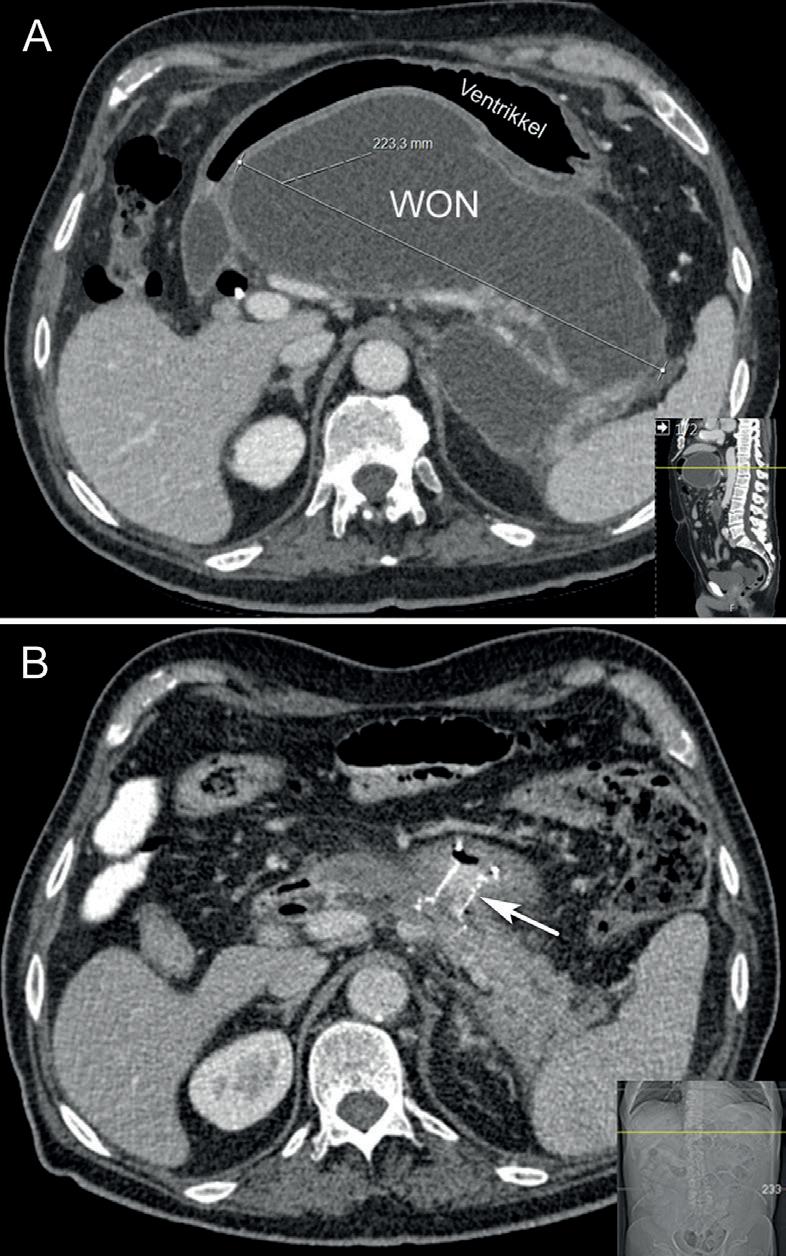

Figur 3. Lumen apposing metall stent (LAMS) lagt fra ventrikkel for drenasje av infisert walled-off nekrose (WON) etter nekrotiserende pankreatitt.

diatermikniv, som muliggjorde direkte punksjon og frigjøring av stent i en enkelt prosedyre uten å bytte instrumenter over en guidewire. LAMS-stenter er korte (10-15 mm) med stor diameter opptil 20 mm, og er dekket slik at de kan fjernes ved behov (figur 3). LAMS gjorde det teknisk enklere å gjøre drenasjer på en trygg måte og førte derfor til at prosedyrene kunne utføres av andre enn «super-spesialister». Utviklingen og utbredelsen i bruken av LAMS har særlig vært drevet frem av dreiningen mot primær endoskopisk behandling av infiserte nekroser i forløpet av alvorlig/ nekrotiserende pankreatitt (6), og EUS-veiledet drenasje (figur 3, 4) har nå blitt første valg og standard behandling ved infiserte “walled-off” nekroser (WON). EUS-veiledet av drenasje av andre abscesser, f.eks. bekkenabscesser sekundært til divertikulitt eller kirurgi, har også vist lovende resultater (7), og egne erfaringer taler for dette kan være et alternativ i situasjoner hvor annen kirurgisk inter vensjon vil unngås. Videre har det kommet flere studier hvor drenasje av galleblære er utført hos pasienter med kolecystitt hvor kirurgisk behandling ikke er aktuelt pga komorbididet eller andre spesielle forhold (8).

Figur 4. Abdominal CT fra pasient med nekrotiserende pankreatitt før drenasje av WON (A) og (B) etter 4-ukers behandling med LAMS (pil).